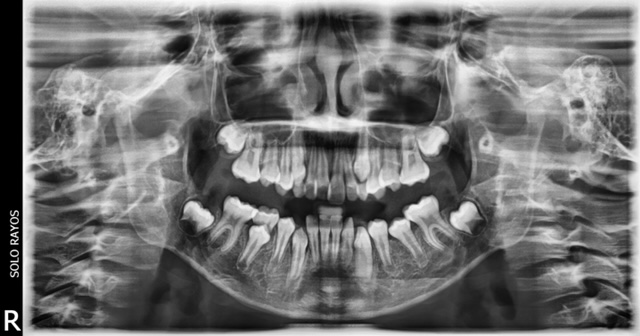

Radiografía Panorámica

Las Rx. Panorámicas requieren una máquina especial que rota alrededor de la cabeza. La radiografía captura los maxilares y los dientes completos en una sola toma. Se utiliza para planear un tratamiento para implantes dentales, verificar si hay muelas de juicio impactadas y detectar problemas mandibulares.